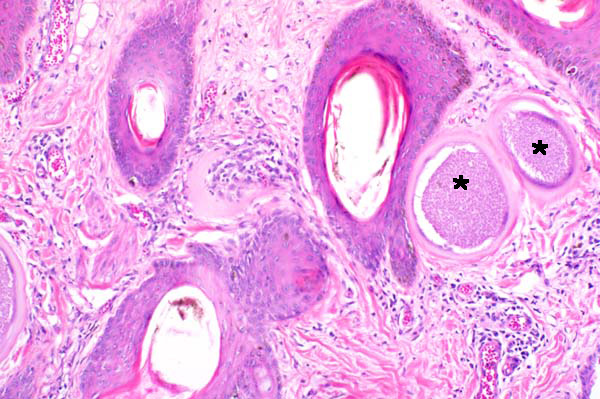

Increased collagen and inflammation surround mildly hyperplastic hair follicles and cysts (asterisks) in the superficial dermis.